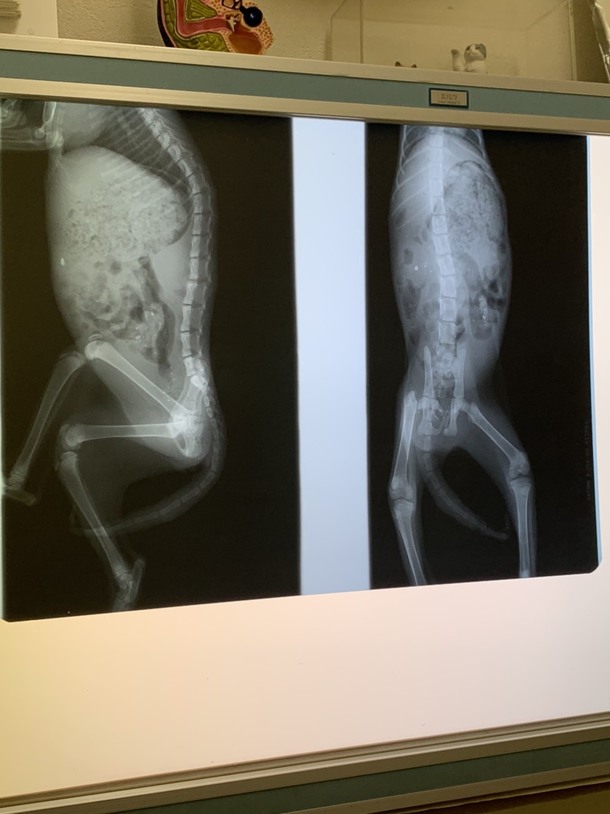

そのルナちゃんを本日6月18日に病院に連れて行ってくれたのですが…尻尾は壊死をおこしている為切断しなければならず、脚も骨折しているため手術が必要との事でした。

脚に関しては今手術をしないと後々歩けなくなってしまうとの事です…。